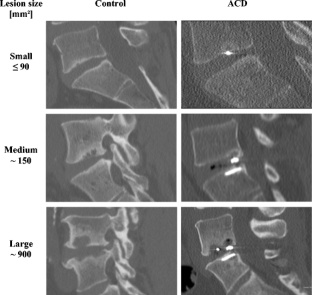

Fig. 1